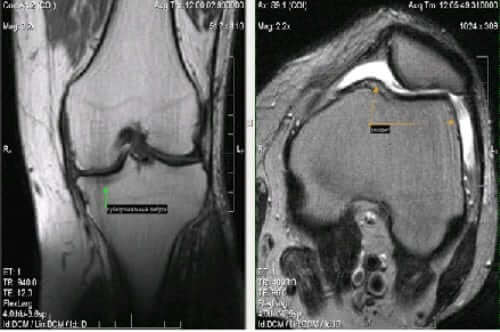

С помощью инструментальных обследований определяется как стадия патологии, так и возможные осложнения. Эти методы используются для уточнения причин заболевания. Наибольшей информативностью характеризуется:

- артроскопия;

- артропневмография;

- МРТ, КТ;

- проведение рентгена.